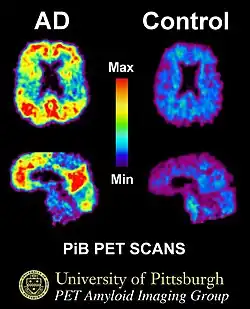

Phonological processing yields phonological codes (or representations) which are then used in speech processing to reach higher-level lexicon representations that are essential for auditory speech comprehension [6]. Strong empirical evidence shows the involvement of the posterior middle temporal lobe regions in accessing lexical and semantic information [6][8][11]. Lesion studies of the posterior temporal lobe have also supported this evidence. Elizabeth Bates and her colleagues studied 101 left-hemisphere aphasic patients and found that lesions to the middle temporal gyrus (MTG) most accurately predicted auditory comprehension deficits, with a significant deficit also observed with dorsolateral prefrontal cortical lesions. Whereas, lesions to the insula and arcuate/superior longitudinal fasciculus affected verbal fluency the most [12]. Functional magnetic resonance imaging studies (see Figure 3 for an example of an fMRI scan) have further implicated the posterior middle temporal lobe regions in semantic processing. In a semantic decision task in research conducted by Jeffrey Binder and colleagues, activations were found in both sides of the STS and almost all of the MTG in the left hemisphere. They also found that this activation spread ventrally across the inferior temporal gyrus (ITG). The authors found further activations in the angular gyrus, anterior and posterior cingulated gyrus, portions of the precuneus, retrosplenial cortex, and cinglulate isthmus in the left hemisphere; as well as subcortical activations in the anterior thalamus in the left hemisphere. [11]. Many positron emission tomography (PET) studies (see Figure 4 for an example of a PET scan) examined the activated areas in response to semantic processing. They too found left lateralized non-STG temporparietal regions; including the MTG, inferior temporal gyrus (ITG), and the angular gyrus [13] [14][15].